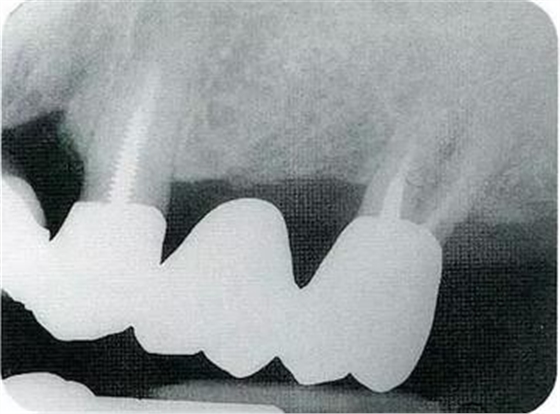

▼圖16-1 ▼圖16-2

圖16-1對(duì)右上6.7分叉部病變處理時(shí),對(duì)包括右上4.5進(jìn)行齦瓣分割,確認(rèn)骨缺失狀態(tài)。右上7頰側(cè)存在著12mm的骨緣下缺失。

圖16-2右上6水平的分叉部病變到達(dá)了III度。